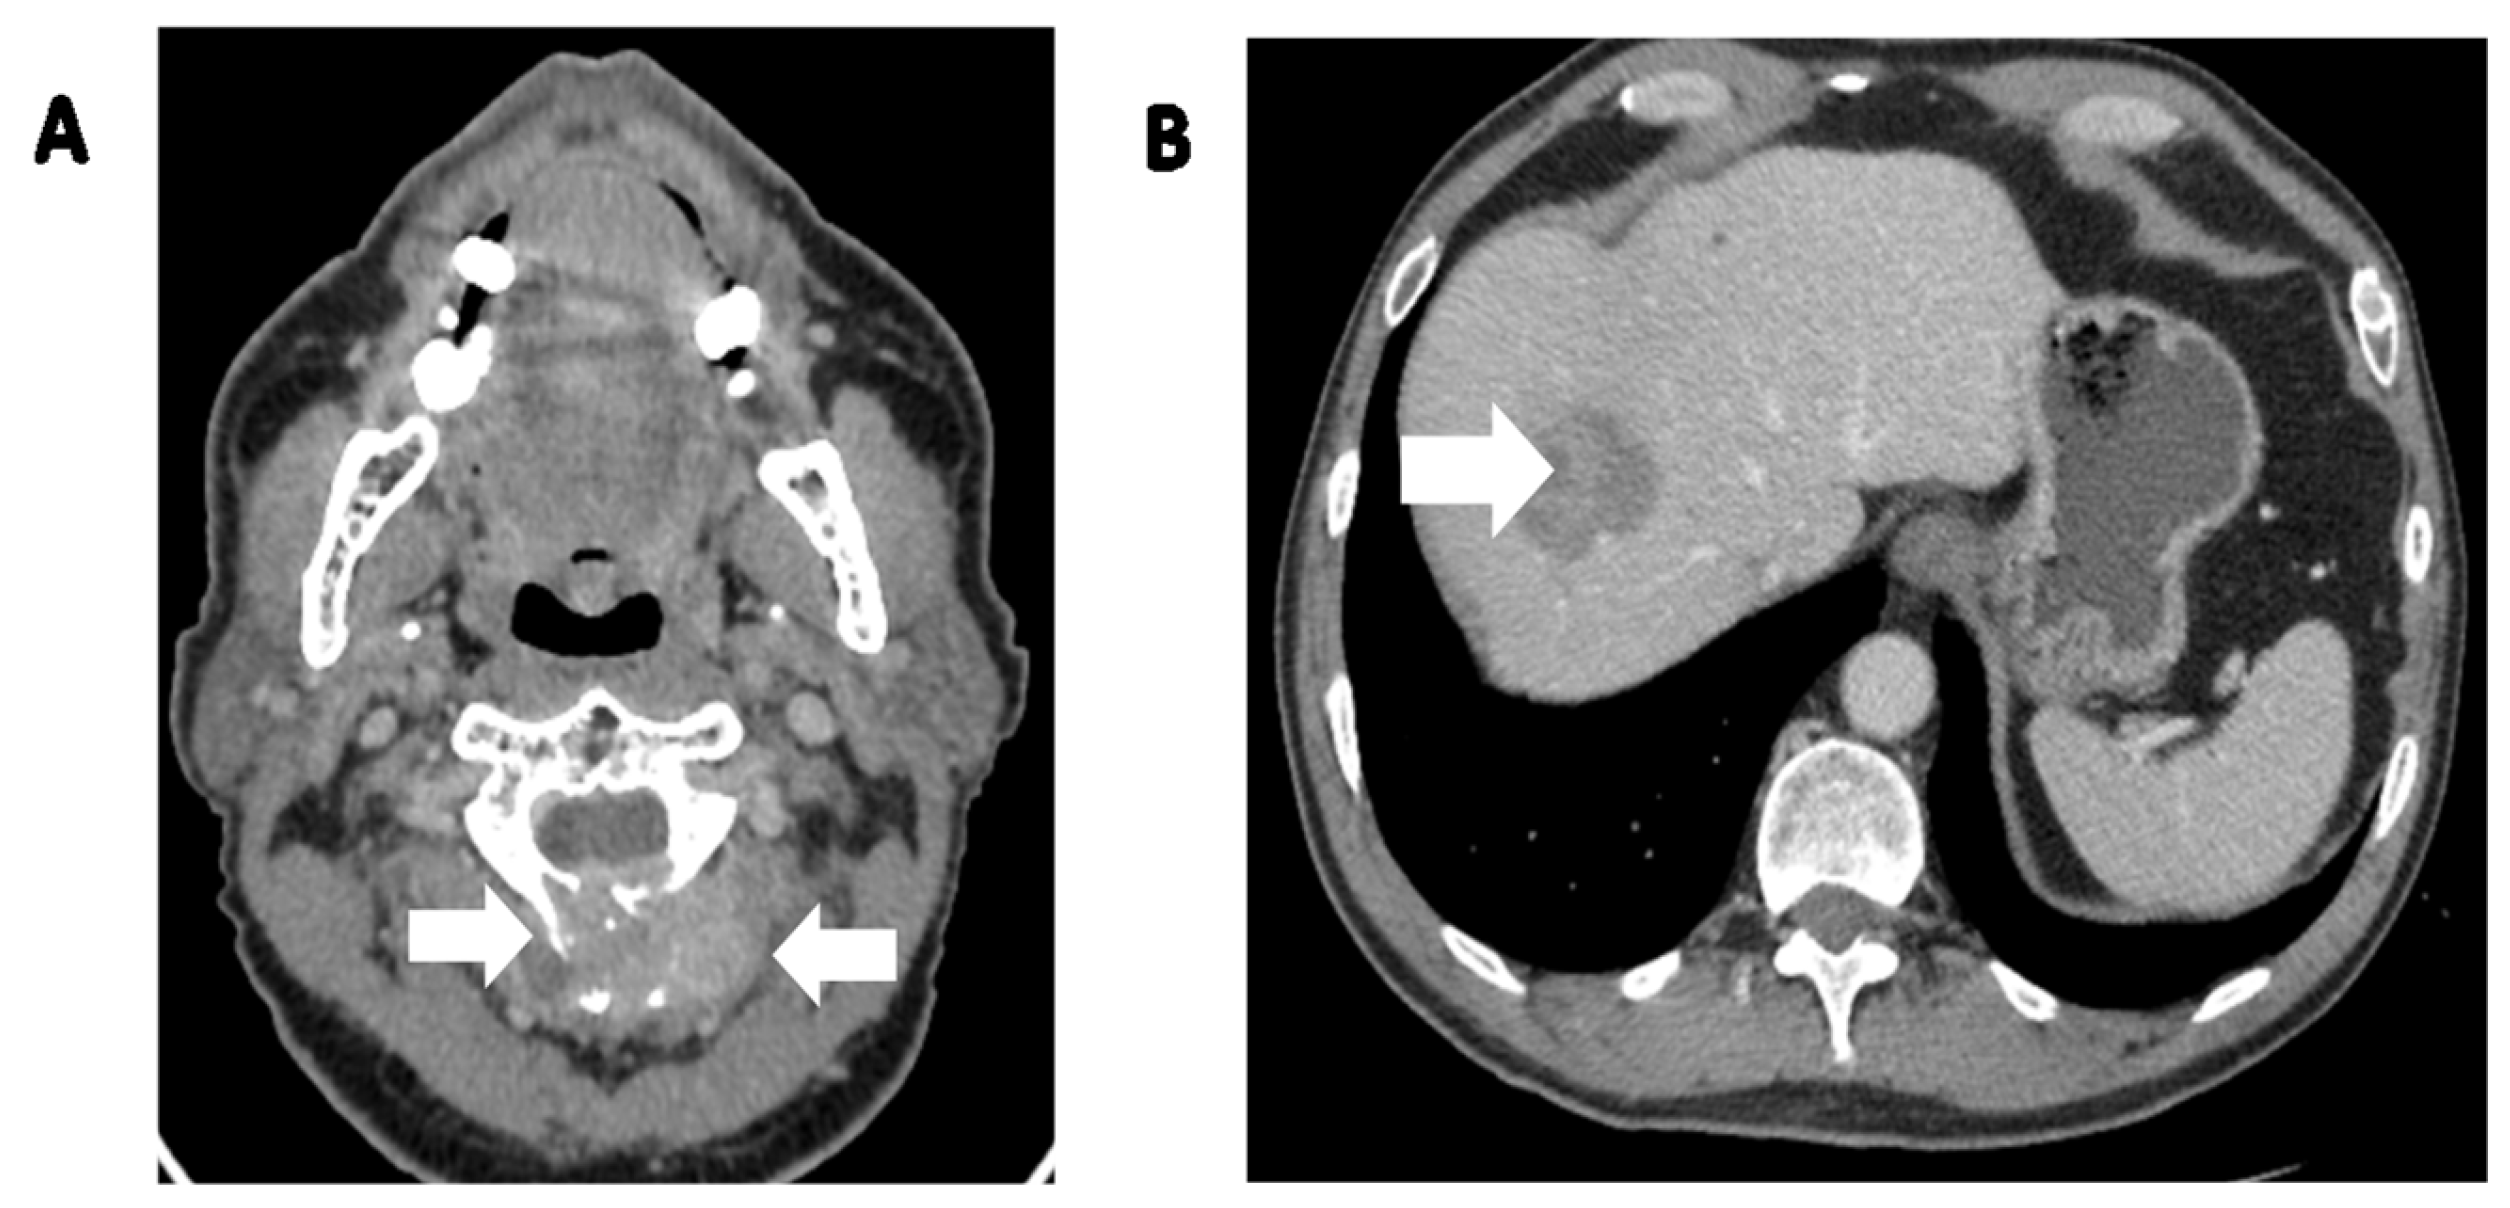

Figure 3.

A 65-year-old patient with locally advanced SFT in parietal bone with infiltration of the superior sagittal sinus with adhesion to the dura mater was admitted in 2022 to begin systemic treatment. Symptoms had begun in March 2019, with a growing subcutaneous tumor in the parietal area. It was initially excised by a dermatologist and diagnosed as lipoma. In February 2022, due to tumor recurrence, the patient underwent a biopsy which was diagnosed as a malignant solitary fibrous bone (SFTB). (A) CT scan, axial view showing the destruction of the parietal bone. (B) CT scan, coronal view showing bone destruction with a soft tissue mass adhering to the skin. (C) CT scan, sagittal view clearly depicting the size of the tumor in relation to the parietal bone and skin.